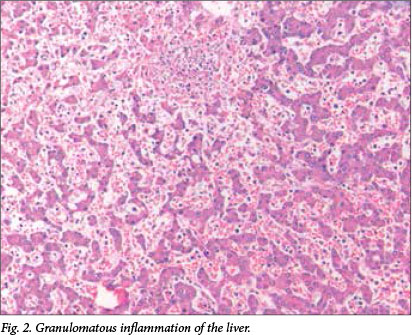

Microscopic examination revealed multiple well-formed granulomas in both lungs (Fig. 1), kidneys, the liver (Fig. 2), brain (Fig. 3) and right adrenal gland. Fungal elements consistent with Candida spp. were seen within these granulomas. The periodic acid-Schiff special stain highlighted the fungal organisms (Fig. 4). Examination of the autolytic tissue from the brain showed an extensive fungal meningoencephalitis (Fig. 3). Examination ofthe thymus revealed parenchymal haemorrhages seen in the first 12 hours following a stressful event. Marked sinusoidal congestion was present in the spleen.